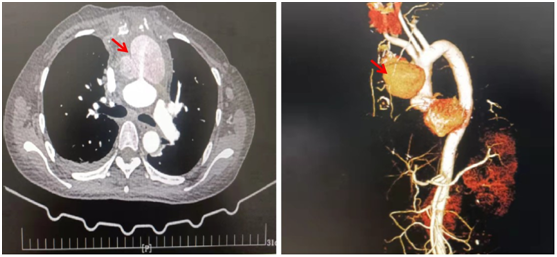

主動(dòng)脈假性動(dòng)脈瘤是由于主動(dòng)脈壁至少一層結(jié)構(gòu)破裂而形成的,它被剩余的血管層和周圍的縱隔結(jié)構(gòu)所包繞。假性動(dòng)脈瘤可在主動(dòng)脈、冠狀動(dòng)脈口、主動(dòng)脈近端或遠(yuǎn)端縫合線形成,也可出現(xiàn)在主動(dòng)脈切口處、主動(dòng)脈插管、主動(dòng)脈鉗夾阻閉鉗處等部位[3,4]。如果不及時(shí)進(jìn)行手術(shù)處理,胸主動(dòng)脈假性動(dòng)脈瘤會(huì)逐漸擴(kuò)張、壓縮和侵蝕周圍結(jié)構(gòu),或成為持續(xù)感染和全身性栓塞的來源[2]。

箭頭所示為主動(dòng)脈假性動(dòng)脈瘤

假性動(dòng)脈瘤的死亡率很高,但在無癥狀的病人中很難識(shí)別,患者只有在復(fù)查CT或MRI隨訪中偶然發(fā)現(xiàn)假性動(dòng)脈瘤,表明術(shù)后復(fù)查的重要性[2]。升主動(dòng)脈假性動(dòng)脈瘤最常見的癥狀是胸痛、心力衰竭和膿毒癥,而氣管受壓常與主動(dòng)脈弓和降主動(dòng)脈的假性動(dòng)脈瘤有關(guān)。較少見的表現(xiàn)包括壓迫或侵蝕周圍結(jié)構(gòu)和形成瘺管。然而,胸主動(dòng)脈假性動(dòng)脈瘤的再次手術(shù)在臨床上具有挑戰(zhàn)性,這取決于其位置和/或形態(tài),以及合適的手術(shù)時(shí)機(jī)。據(jù)報(bào)道未進(jìn)行手術(shù)處理的胸主動(dòng)脈假性動(dòng)脈瘤的死亡率為29~46%[3]。